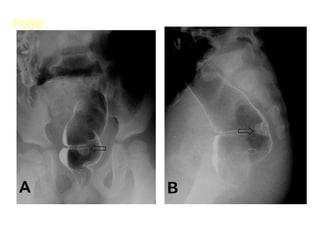

Tuï khí sau phuùc maïc

sau sinh thieát